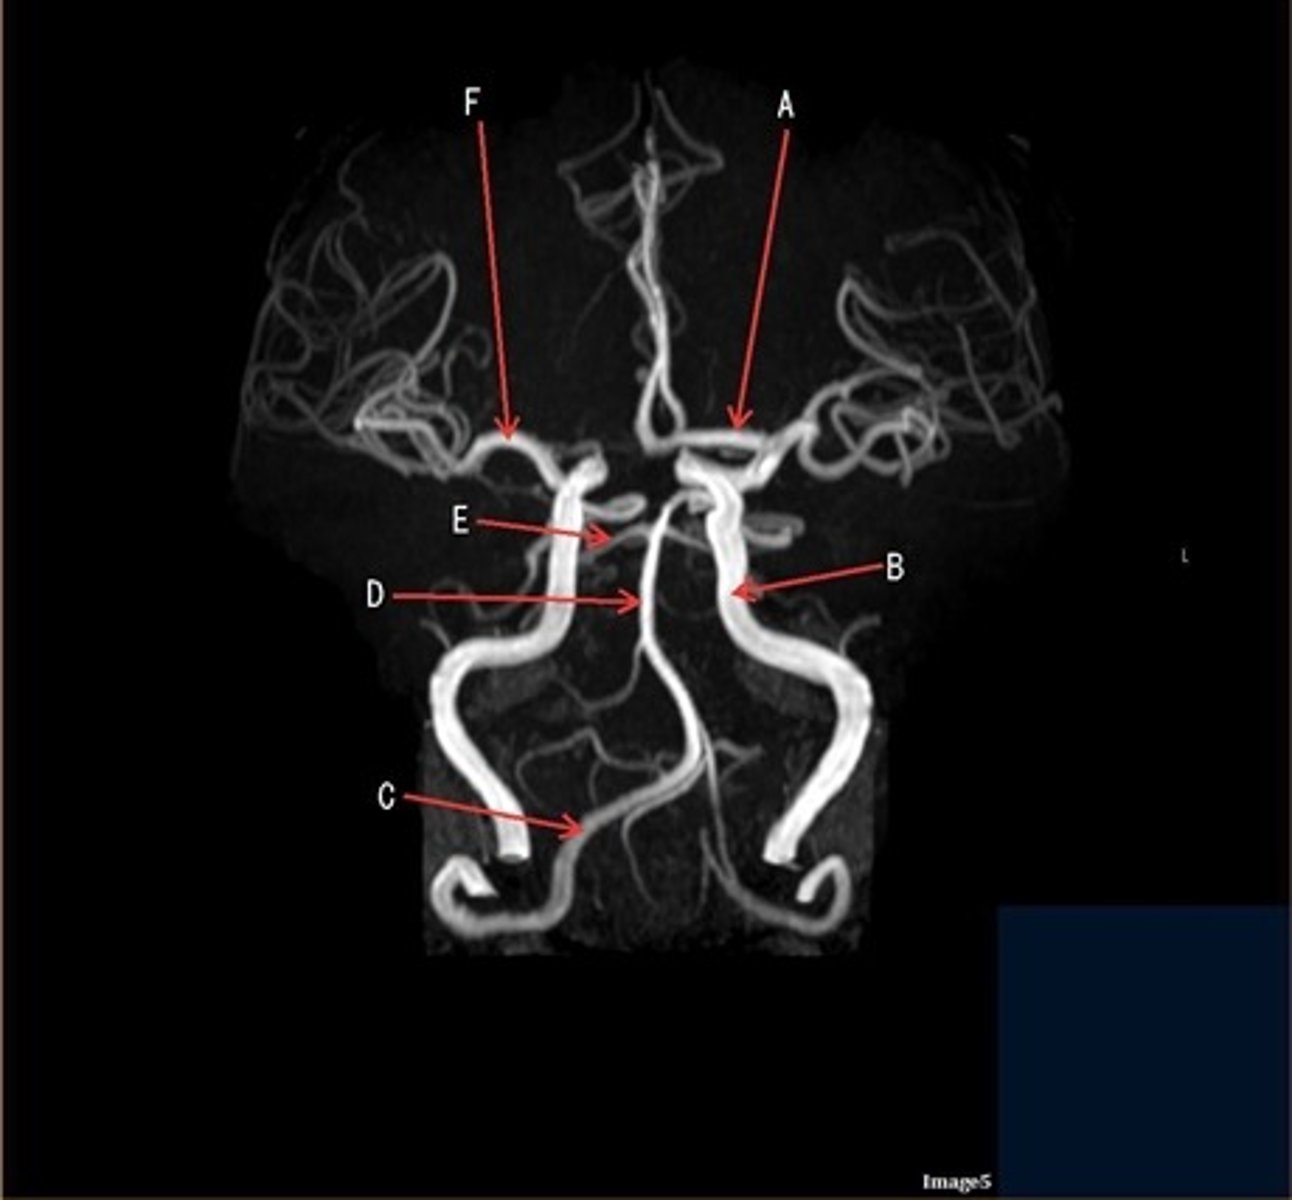

A

A- anterior cerebral artery

B

B- internal carotid artery

C

c- vertebral artery

D

D- basilar artery

E

E- posterior cerebral artery

F

F- middle cerebral artery